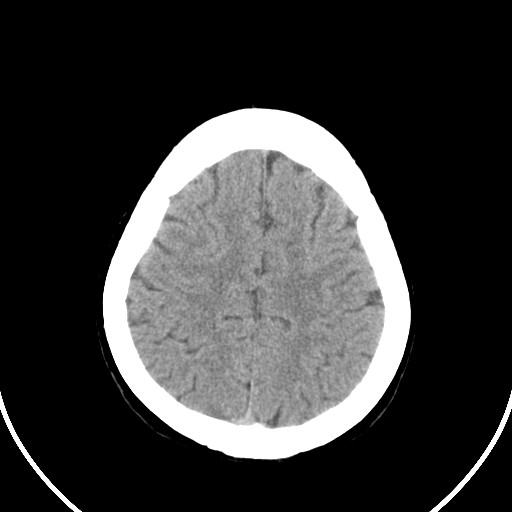

标题: CT21850:女,56岁,右中指淤肿,右手麻痹1天

女,56岁,右中指淤肿,右手麻痹1天

双侧侧脑室额角旁对称性略低密度影,边缘模糊,无占位效应,考虑轻度脑白质稀疏症(病人有高血压吗).,右枕叶低密度影多为伪影,不放心薄扫一下.

考虑脑白质病。

考虑脑白质病